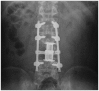

Rapid progression of solitary plasmacytoma to multiple myeloma in lumbar vertebra

The prognosis of solitary plasmacytoma varies greatly, with some patients recovering after surgical removal or local fractional radiation therapy, and others progressing to multiple myeloma years later. Primary detection of progression to multiple myeloma is important in the treatment of solitary plasmacytoma. There have been several analyses of the risk factors involved in the early progression to multiple myeloma. We describe one case of solitary plasmacytoma of the lumbar vertebra that was treated with surgical decompression with stabilization and additional radiotherapy. The patient had no factors associated with rapid progression to multiple myeloma such as age, size, immunologic results, pathological findings, and serum free light chain ratio at the time of diagnosis. However, his condition progressed to multiple myeloma less than two months after the initial diagnosis of solitary plasmacytoma. We suggest that surgeons should be vigilant in watching for rapid progression to multiple myeloma even in case that the patient with solitary plasmacytoma has no risk factors for rapid progression to multiple myeloma.